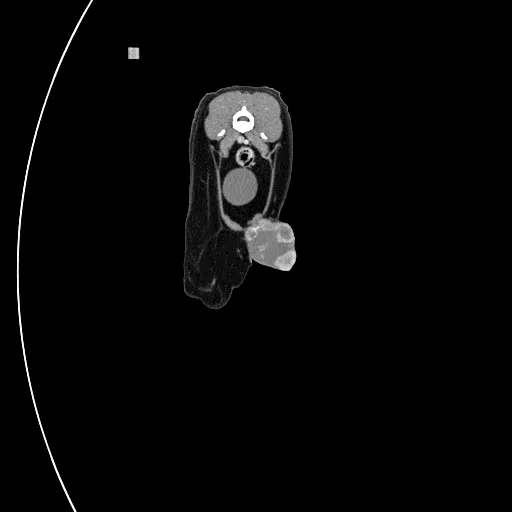

FIGURE 2

CT scan of the same cat with injection site sarcoma, confirming the flank fold tumor is invading the body wall